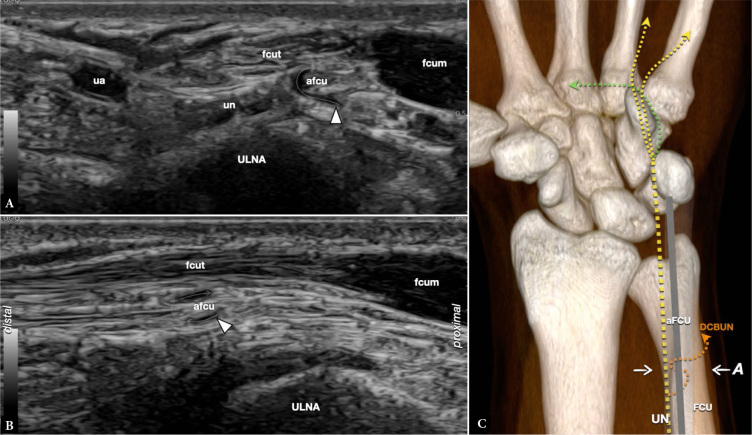

Results: Between October 2019 and October 2023, six cases were found in five patients, where ultrasound demonstrated previously undescribed-at-imaging anatomical variations of the distal ulnar nerve on six distal forearms. The variant was symptomatic in three cases in which possible distal compression was clinically suspected. A branch of the ulnar nerve made a loop around the flexor carpi ulnaris, which also presented with a variation of normal anatomy. In symptomatic patients, the diameter of the aberrant branch (retrospectively measured) was significantly enlarged.

Conclusions: High-resolution ultrasound can accurately demonstrate ulnar nerve variants even when only small nerve fascicles are involved, which may be clinically relevant and misinterpreted. Loops of the ulnar nerve are rare, but likely under-recognized. We think that symptoms are generally tolerated by patients if the motor branch of the ulnar nerve is not affected, as in our cases.